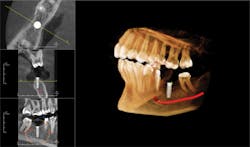

I attend the Texas Dental Association meeting each year and it proved to be an excellent time to meet with vendors. I spoke with almost every company that has a cone beam unit. I kept coming back to Instrumentarium. The OP300 Maxio had the field of view we needed-from a targeted 5 x 5 cm scan to a comprehensive condyle-to-condyle view that includes the airway-and I liked the clean look of the machine. What finally sold me was the rep we worked with, Jimmy. He was a superstar. We've had the unit in our practice for almost a year now and he's taken care of us every step of the way. With training, support, and cost, he's provided excellent service and proven to be extremely knowledgeable.

The OP300 Maxio offers extended fields of view for diagnosis and treatment of the entire maxillofacial region.

In both my cone beam purchases (seven years ago and again last summer) my interest in the technology was driven by the opportunity to offer the best possible clinical options to our implant patients. Today, we're using the unit for more than we dreamed, including root canals, abscesses, and other structural issues. The common value across all those procedures is information. Not only does it give me confidence in my clinical approach, it makes it possible for the entire dental team to get behind the treatment we offer. Before 3-D, we didn't know what we didn't know.

Selecting the precise area of interest is as easy as pointing.